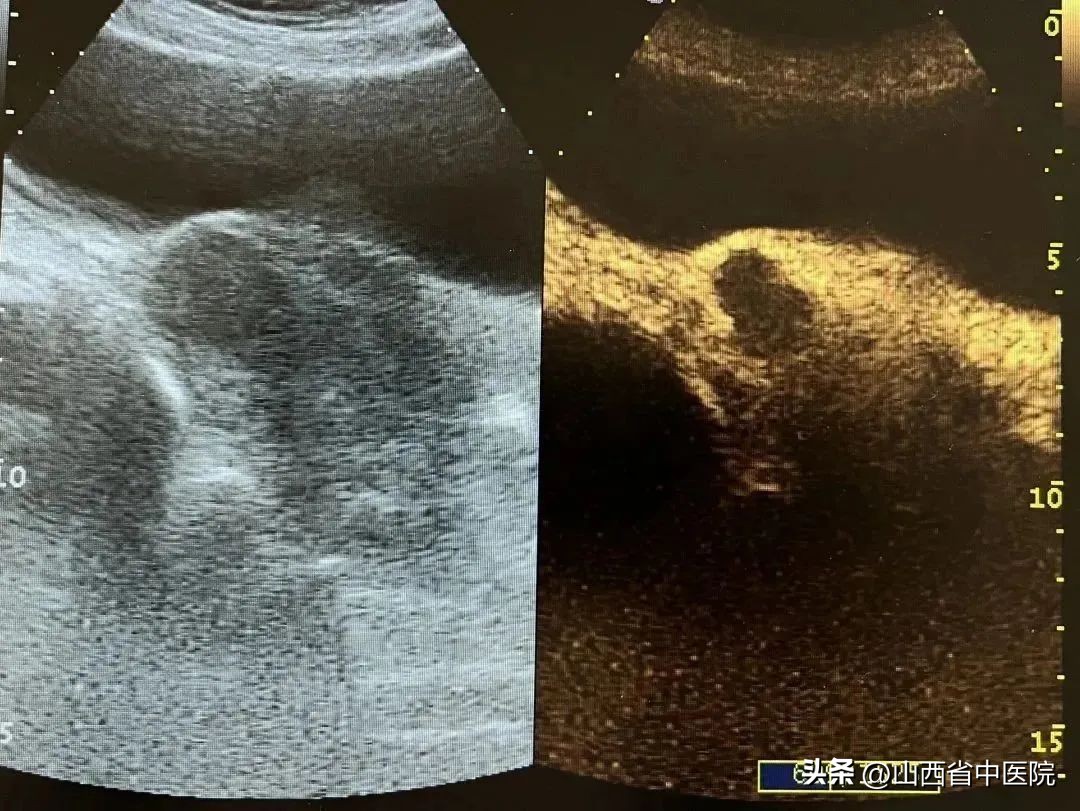

2023年2月8日,市民李女士和张女士就通过山西省中医院妇产科引进的“海扶刀”技术成功治疗了子宫腺肌瘤(5cm)和子宫肌瘤(3cm,5cm)。在“海扶刀”的整个治疗过程中,医生操作仪器,对准影像中出现的肿瘤组织,一个个实现“定向*破爆**”,就杀死了患者体内的子宫肌瘤。

术后疗效:瘤体凝固性坏死,无血流灌注,疗效明显。

海扶手术是高能聚焦超声消融手术,属于无创的局部性治疗方法。利用彩超精准定位病灶,将体外低能量的超声波聚焦于病灶,形成高能量的焦点,使病灶组织凝固性坏死,同时不伤害正常组织,从而达到无创治疗病灶的目的。